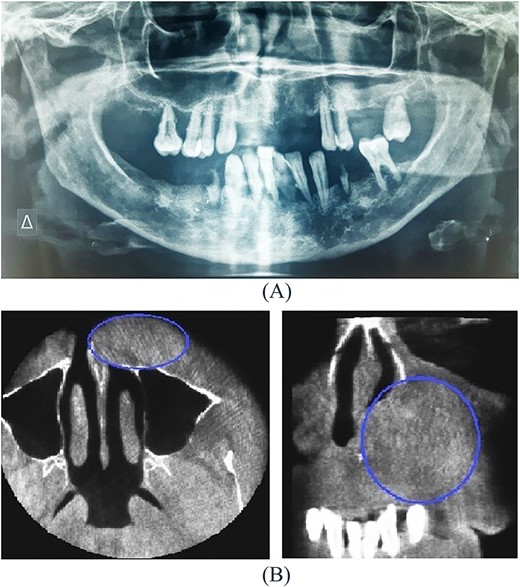

A 54-year-old-Caucasian female was referred to our department with a swelling of the left maxillary area (Fig. 1), actively inflaming. Antibiotics were prescribed, and after a week, the swelling persisted but was painless, roundish, fluctuant in palpation, sizing ~3 cm in diameter. The overlying mucosa was normal and mobile over the lesion. Clinical examination also revealed an extraoral asymmetry over the nasolabial sulcus because of the presence of this lesion causing obstruction of the left nostril. The patient presented with poor oral hygiene and the orthopantomogram revealed periodontal disease (Fig. 2a). CBCT imaging revealed a low density, ovoid, cystic soft tissue mass of 3.4 × 2.3 × 3 cm in close contact with the alar base. The maxilla near the lesion appeared concave, because of the cyst’s pressure, but without erosion (Fig. 2b). The patient was advised to undergo a contrast-enhanced computed tomography (CT) scan, but she did not wish to perform any other imaging study. The patient’s medical history was non-contributory.